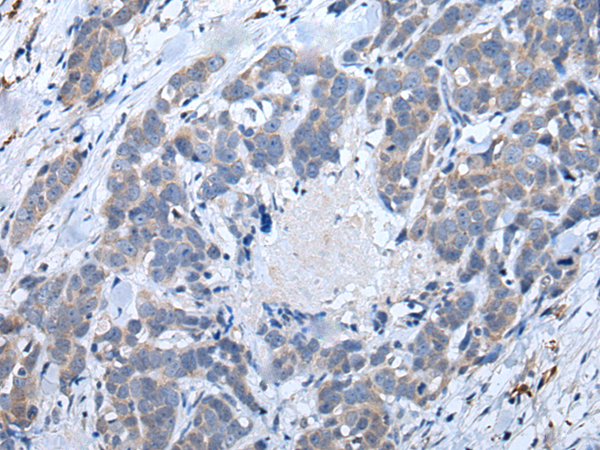

ELISA, IHC |

IHC positive control: |

Human ovarian cancer and human thyroid cancer |

IHC Recommend dilution: |

40-200 |